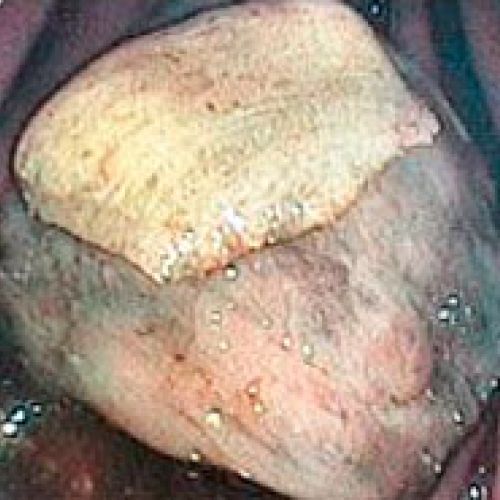

Endoscopia rígida y endoscopia flexible

En CiruVET realizamos procedimientos diagnósticos, como las endoscopias de última generación

En CiruVET contamos con el equipo necesario para los diferentes procedimientos diagnósticos y terapéuticos a nivel respiratorio y digestivo. En resumen, realizamos las siguientes pruebas diagnósticas: